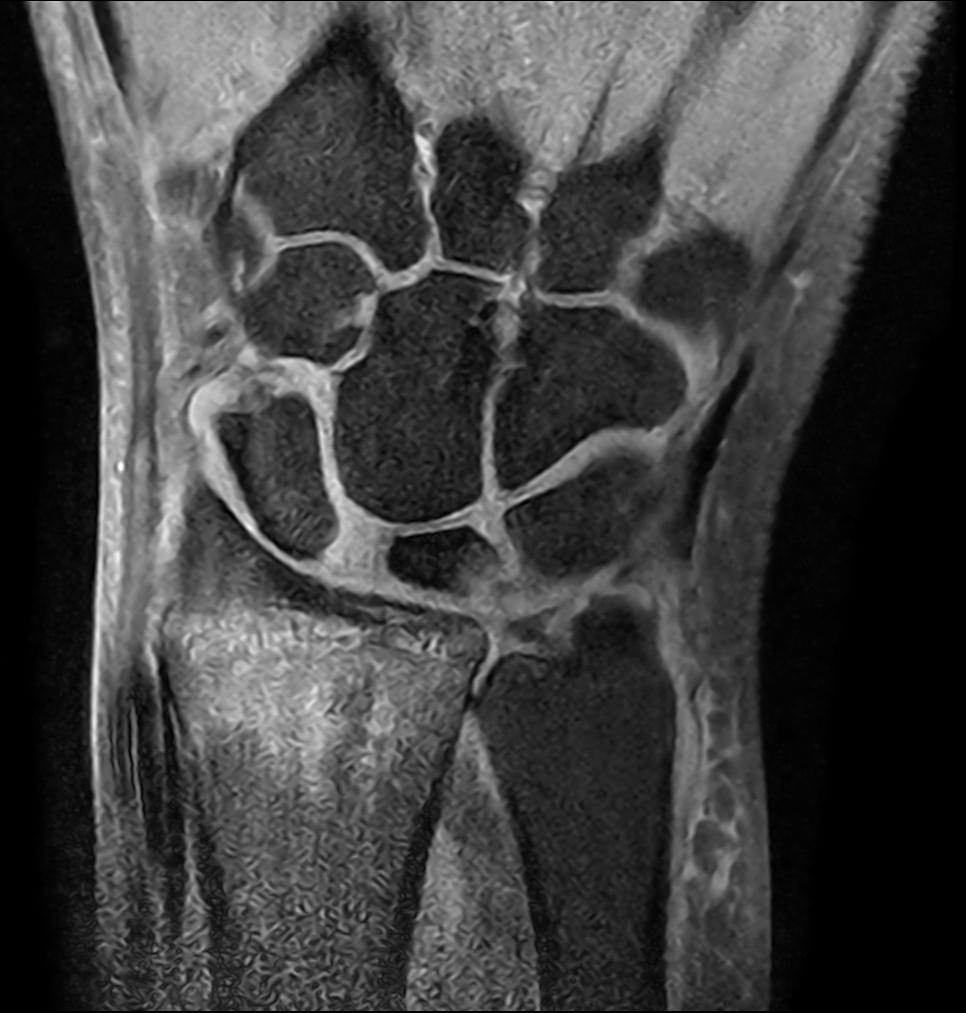

Patient with a wrist fracture. Compressed SENSE is used in all sequences, reducing the scan time while maintain equal image quality compared to scans without Compressed SENSE. 3D sequences have been added to this ExamCard with a comparable in-plane resolution but much thinner slices. Due to the shorter scan times that can be achieved thanks to Compressed SENSE, these 3D sequences could potentially replace the 2D sequences providing more confidence in making the diagnosis.

2D Coronal PDw SPAIR

3D Coronal PDw SPAIR